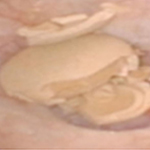

[ ü¿ÜÃæ°ÝÆÄ¼â¼®¼úÀÇ ½Ã¼ú ¸ð½À(ÁÂ), ¿ø¸®(¿ì) ]

¿ä°üÀ¸·Î ºüÁ®³ª°¡Áö ¸øÇÏ´Â Å« °á¼®

Ãæ°ÝÆÄ¸¦ ÀÌ¿ëÇØ °á¼®À» Àß°Ô ºÐ¼âÇÔ

ºÐ¼âµÈ °á¼® Á¶°¢ÀÌ ¼Òº¯À¸·Î ÀÚ¿¬ ¹èÃâµÊ